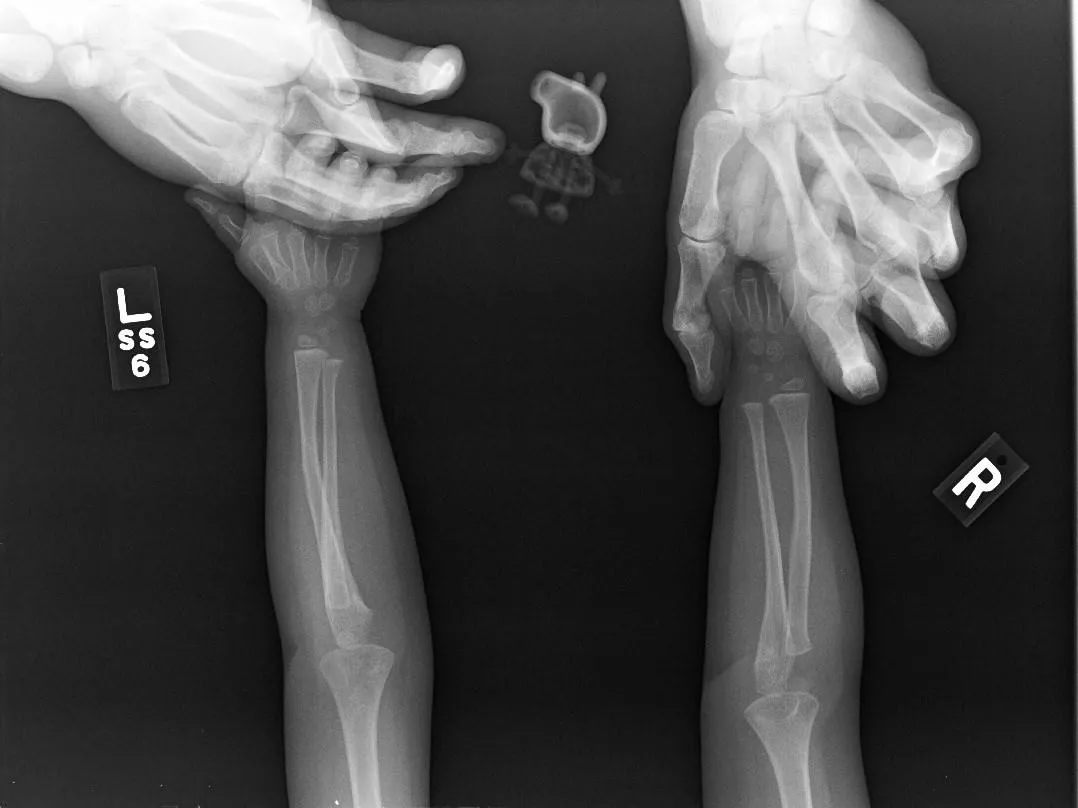

Ничего удивительного! Просто девочка отказалась делать снимок без своей любимой игрушки – свинки Пеппы

Фото imgur